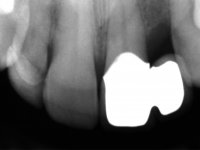

Fifty year old male patient, non-smoker. Carries a Maryland Bridge replacing tooth 2.2. "Maryland wings" are metallic and the dental surfaces in contact with them are infiltrated. Tooth 2.1 had a feldspathic ceramic veneer covering the vestibular surface. Tooth 1.2 presented a feldspathic ceramic veneer with exposed cervical margin. The edentulous space corresponding to tooth 2.2 is narrow and tall. Patient presents an open anterior bite, good oral hygiene and reasonable periodontal health.

A two element bridge was suggested, using tooth 2.1 as abutment and tooth 2.2 as cantilever pontic. Cantilever bridge with ceramic-coated Zr infrastructure.

Arcade prints were made with irreversible hydrocolloid, for the lab to prepare an acrylic provisional bridge, with tooth 2.1 as abutment and tooth 2.2 as cantilever pontic. A palatal support was made to be bonded with the palatal surface of tooth 2.3. After removal of the Maryland bridge and the vestibular veneer from tooth 2.1, the dental abutment was re-prepared by making the cervical finish line intrasulcular. The provisional bridge made in the lab was relined on the mouth with self-curing acrylic and composite resin. During 6 weeks the soft tissues were worked and stabilized, preparing the consultation for impression. In this session, gingival separation was performed with kaolin paste, using the provisional bridge to compress the material into the gingival sulcus. Impression was performed using wash technique, and the provisional bridge was placed. At the end of the consultation, an impression was made from the provisional bridge placed in the mouth, using irreversible hydrocolloid. The patient had approved the aesthetics of the provisional. This information was passed on to the lab, where the work followed a silicone index, based on the shape and arrangement of the provisional bridge, approved by the patient. The cantilever bridge was built with a Zr infrastructure, with particular care in designing the connector. After being tried and approved by the patient, the prosthetic was cemented in the mouth with resin modified glass ionomer.